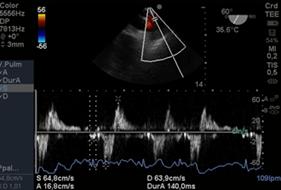

Onda E del anillo mitral (Figura 18): cuando la IM es severa hay hiperflujo generando una onda por encima de 1.5cm/s.

Figura 18 imagen medioesofágica de 2 cámaras a 87° con gradienteelevado, onda E mitral de 2m por IM severa holosistólica (Doppler Continuo).